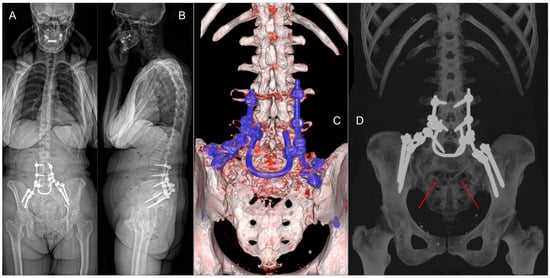

In June 2024, the patient presented to the Emergency Department with acute urinary retention, necessitating the placement of an indwelling urinary catheter. Subsequent MRI (Figure 1A–D) and CT scans confirmed progression of the sacral lesion with significant compression of sacral nerve roots. Based on the clinical and radiological findings, lumbopelvic fixation (LPF) was planned, including nerve root decompression and intralesional resection of the sacral lesion (Figure 1E). The surgical procedure had a total duration of 250 min, with intraoperative blood loss of 180 cc.

Figure 1. Preoperative MRI of the sacral metastatic lesion, in sagittal (A) and axial (BD) planes. (E) Three-dimensional reconstruction of the planned LPF, including nerve root decompression and tumor resection.

Figure 6. (A,B) Post-operative standing X-ray. (C,D) Six-month 3D CT scan reconstruction demonstrating the stability of the LPF and the residual sacral defect (red arrows).